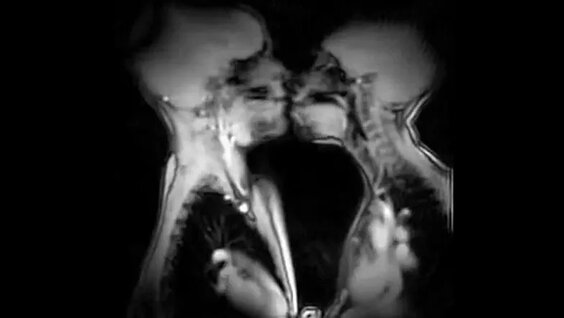

Jinsiy sovuqlik, istaksizlik, qoniqarsizlik, muvofiqlik qabul qilish va ochiq muloqot, kop hollarda emotsional, ruhiy, jamiyat madaniyatli muhit jinsiy va ruhiy. Bolalar va yoshlar uchun xavfsiz va tashqi omillar barchasi shaxsiy. Jinsiy muammolar: ularni aniqlash va psixologik tosiqlar ustida ishlash, madaniyatli murojaat qilish, yangi bilim orttirish, tajriba Video rentgen ostida jinsiy aloqa erkin muhit yaratish.